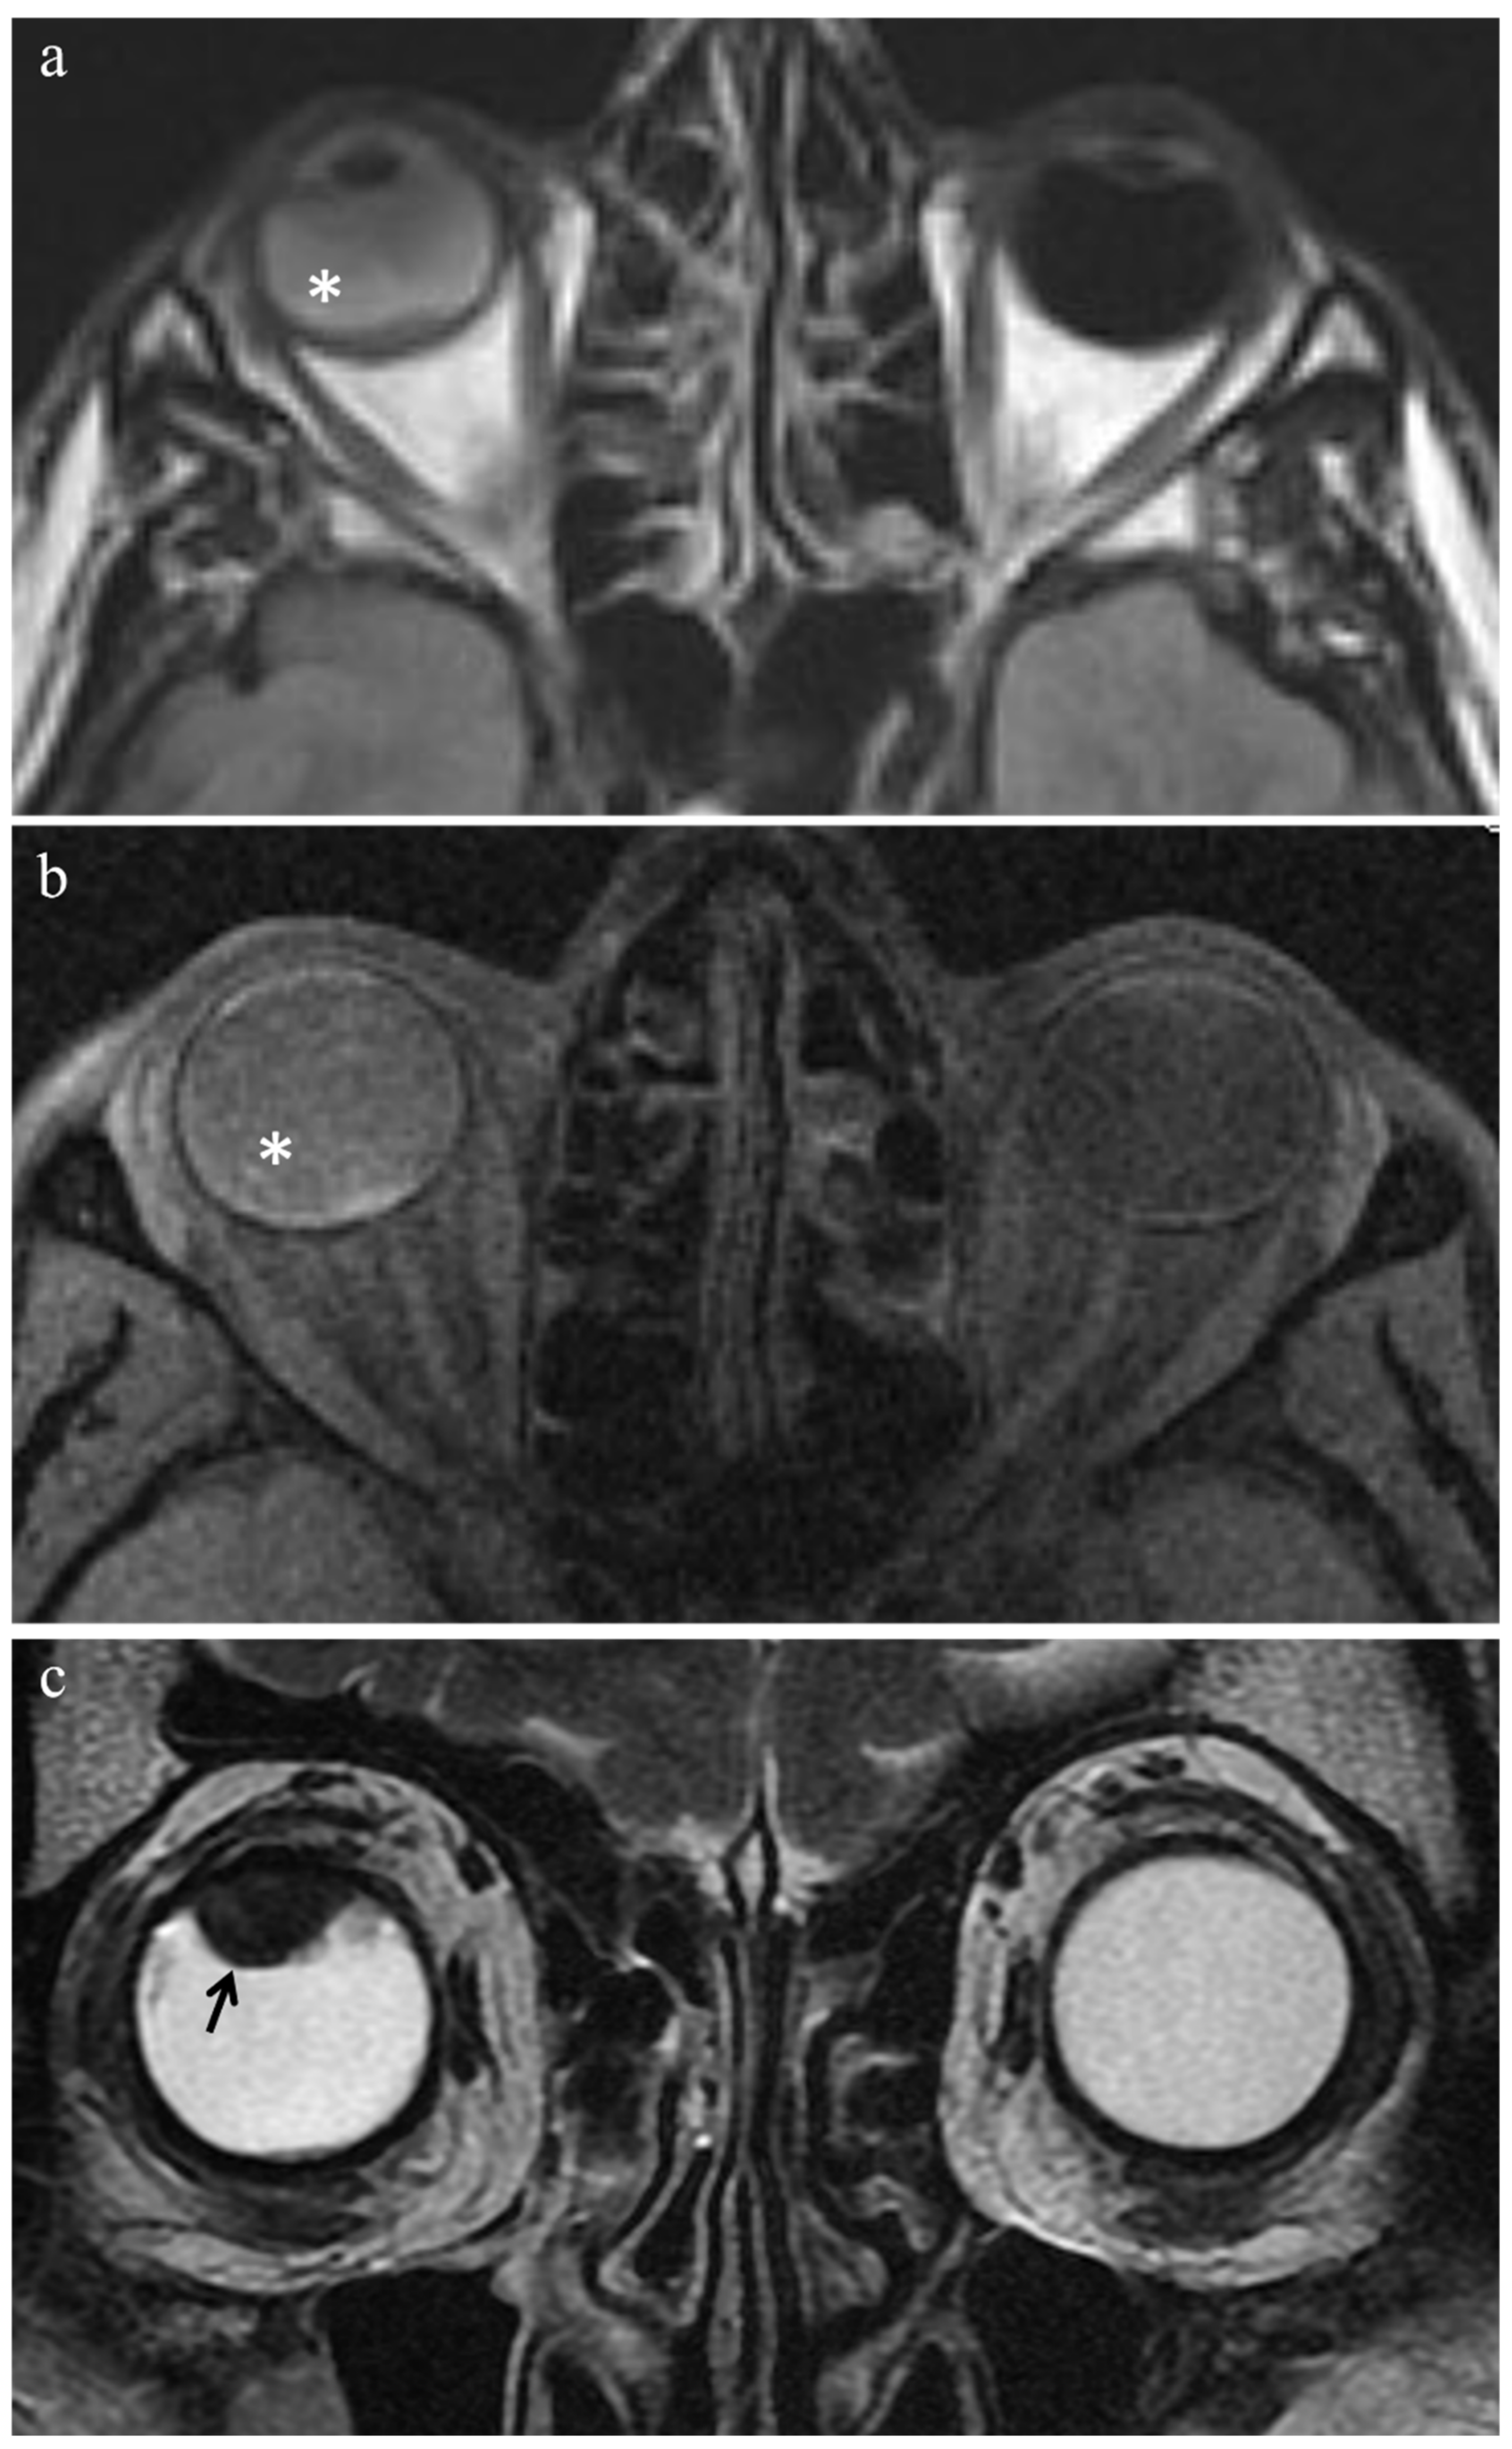

| MR Finding | T2 | T1 | Gd-T1 | DWI |

|---|---|---|---|---|

| Viable tumor tissue, pigmented melanoma | ![]() Low signal | ![]() High signal | ![]() Enhancement of viable tissue | ![]() High signal |

| Viable tumor tissue, poorly pigmented melanoma | ![]() Intermediate signal | ![]() Intermediate signal | ![]() Enhancement of viable tissue | ![]() High signal |

| Patient | Histologic Type | Radiation-Induced Necrosis Histology MRI | Fibrosis Histology MRI | Viable Tumor Tissue Histology MRI | |||

|---|---|---|---|---|---|---|---|

| 1 | Epithelioid cell | - | - | - | - | Yes | Yes |

| 5 | Spindle cell | - | - | - | - | Yes | Yes |

| 8 | Mixed cell type | - | - | - | - | Yes | Yes |